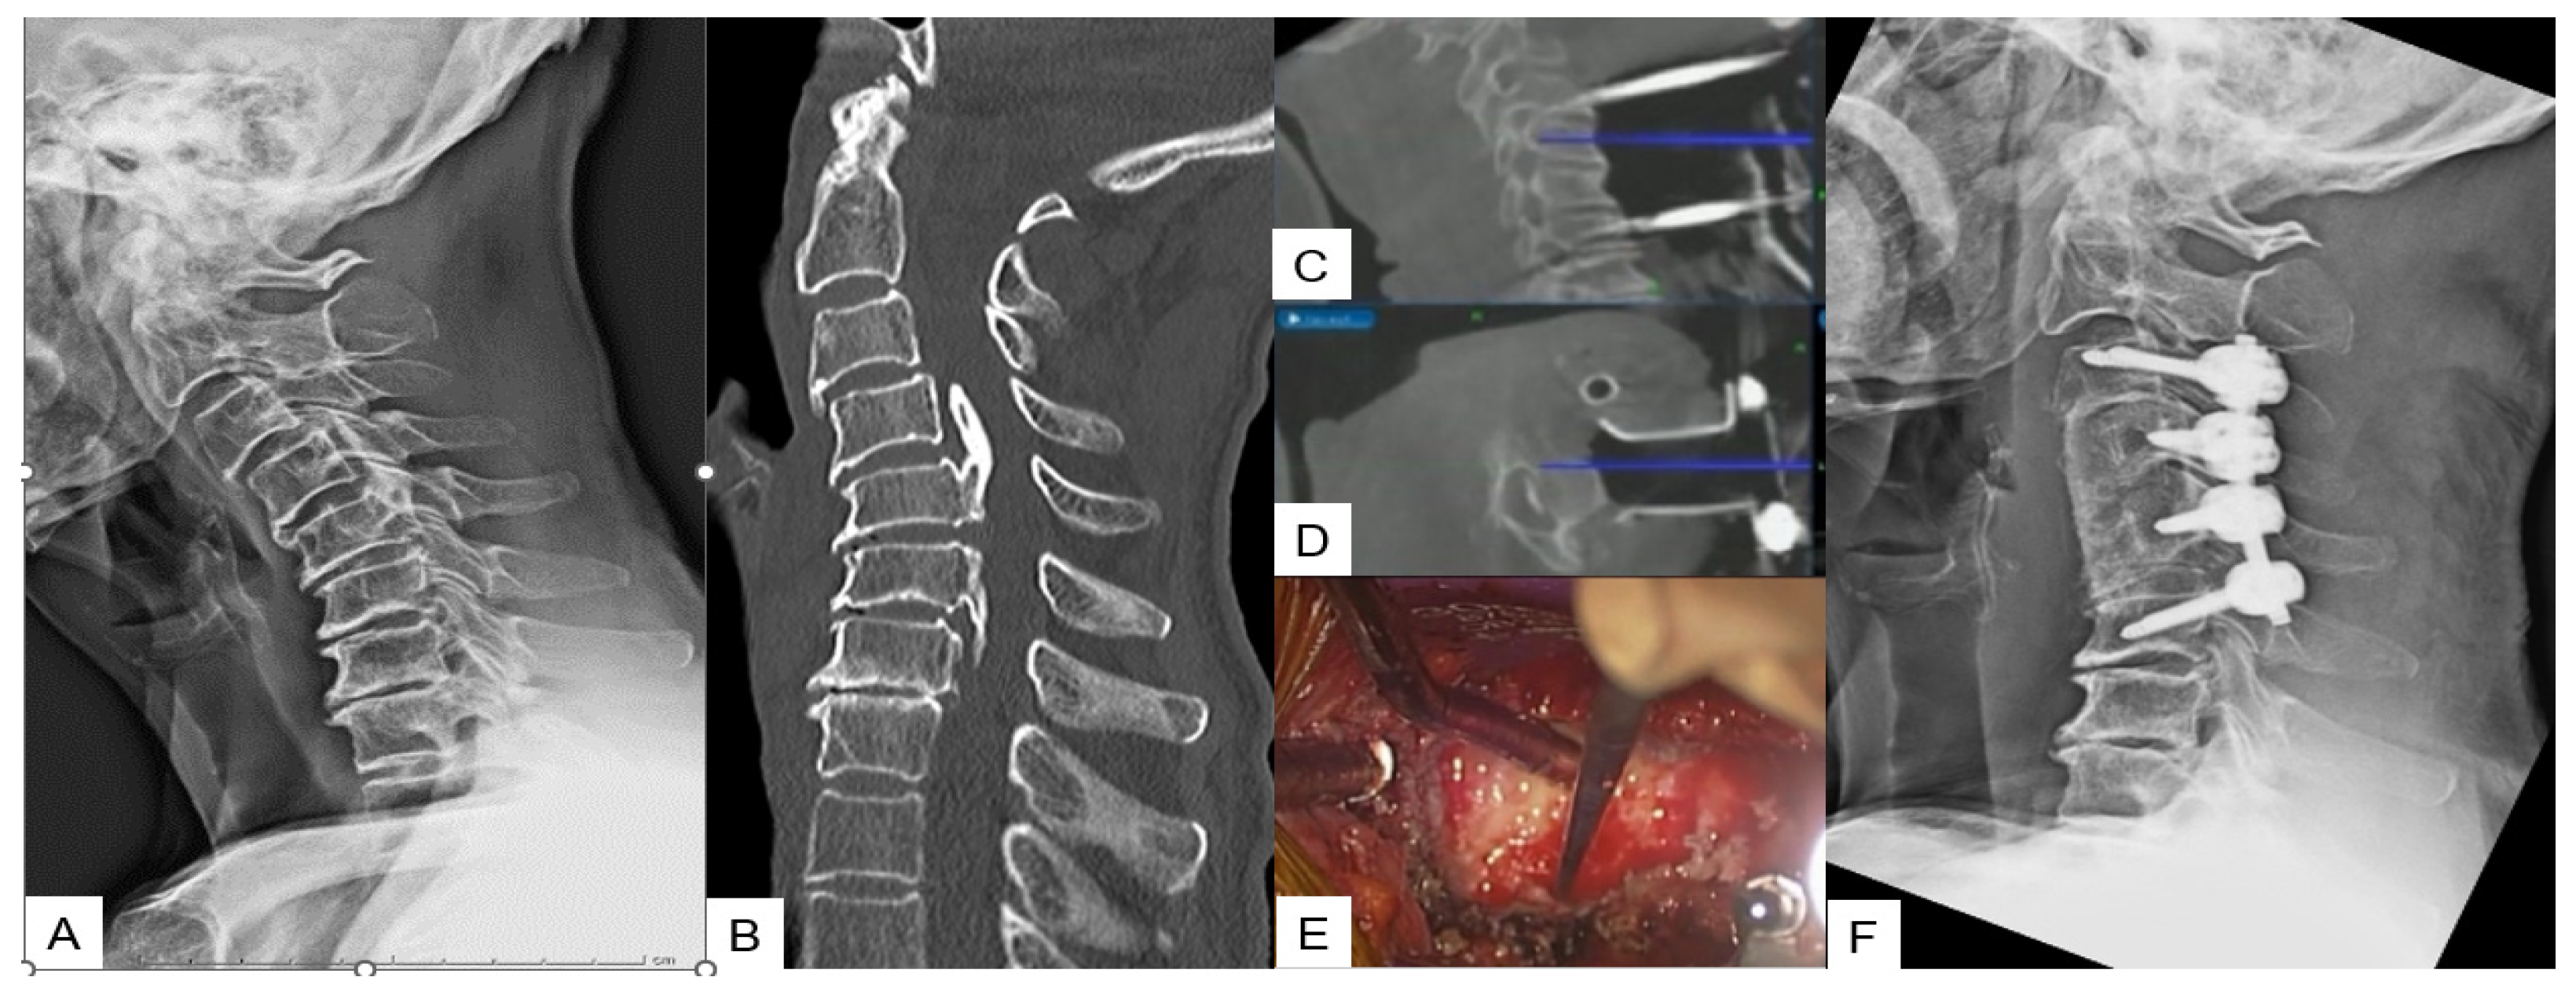

OPLL Resection

- Tanaka, M.; Suthar, H.; Fujiwara, Y.; Oda, Y.; Uotani, K.; Arataki, S.; Yamauchi, T.; Misawa, H. Intraoperative O-arm navigation guided anterior cervical surgery; A technical note and case series. Interdiscip. Neurosurg. 2021, 26, 101288. [Google Scholar] [CrossRef]